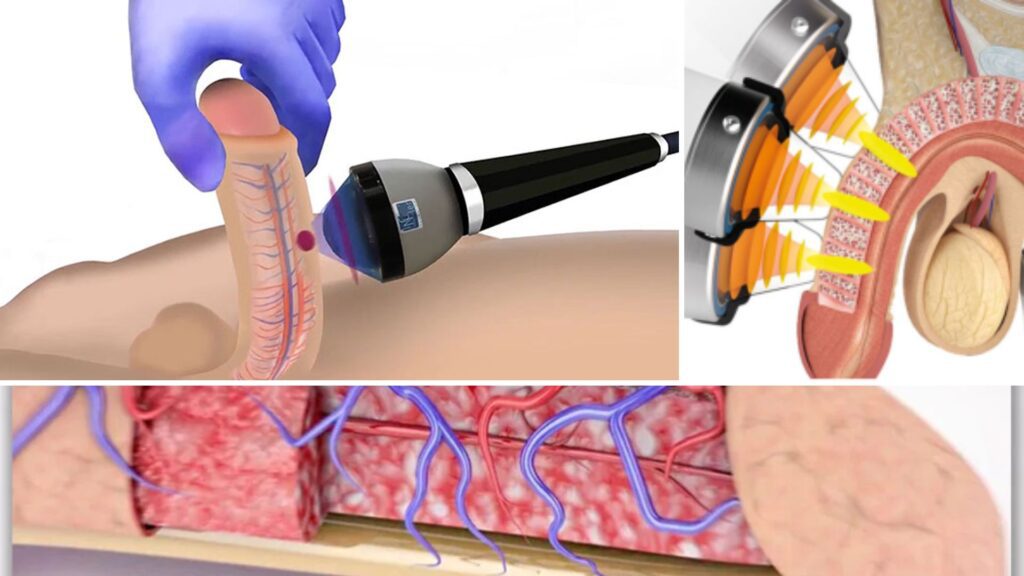

Real Erectile Recovery Comes from These Three Therapies

Across thousands of successful cases, three physical treatments consistently stood out:

- Targeted stimulation to increase blood flow and reawaken dormant sexual nerves.

- Heat therapy to expand blood vessels and flood the area with oxygen-rich blood.

- Gentle pulsing/compression to support circulation and long-term nerve repair.

When used together, these three methods don’t just cover up symptoms — they create the ideal environment for real erectile and nerve recovery.

Thanks to new advances in at-home male wellness technology…

You can now get all three treatments — stimulation, heat therapy, and gentle pulsing/compression — packed into a single, easy-to-use device.

Meet the EMSense “Triple Therapy” Male Wellness Device

At first glance, EMSense looks like a simple wrap designed for the pelvic region.

But the moment you turn it on, you feel the difference.

First, a soothing therapeutic warmth spreads through the area.

Then, gentle stimulation pulses awaken blood flow, encouraging fresh, oxygen-rich circulation where you need it most.

Meanwhile, comfortable compression provides steady support — helping your nerves and blood vessels respond like they used to.